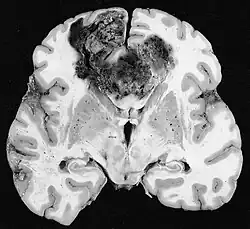

Glioblastomy

Nejčastějšími a maligními nádory z gliových buněk jsou glioblastomy. Skládají se z heterogenní masy špatně diferencovaných buněk astrocytomu hlavně u dospělých. Obvykle se vyskytují v mozkových hemisférách, vzácněji v mozkovém kmeni nebo míše. Kromě velmi vzácných případů, jako všechny mozkové nádory, nepřesahují struktury centrálního nervového systému.

Glioblastom může vzniknout z difuzního (II. stupně) nebo anaplastický astrocytom (III. stupeň) rozvíjet. V druhém případě se nazývá sekundární. Pokud se však objeví bez předchozího zhoubného nádoru nebo důkazu o předchozím zhoubném bujení, označuje se jako primární. Glioblastomy se léčí chirurgicky, ozařováním a chemoterapií. Jsou obtížně léčitelné a jen málo případů přežívá déle než tři roky.